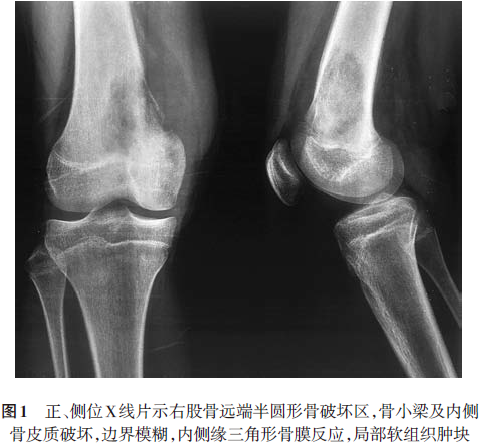

显示心、肺、膈均未见明显异常。正、侧位X线片(2008.6.14)示右股骨远端可见半圆形骨破坏区,骨小梁及内侧骨皮质破坏,边界模糊,内侧缘三角形骨膜反应,局部软组织肿块,提示右股骨恶性肿瘤,膝关节未见明显异常(图1)。CT(2008.6.17)示右侧股骨下段干骺端骨质密度不均匀,内侧骨皮质破坏,骨膜增厚外突(图2)。MRI(2008.6.16)示右侧股骨远端干骺端内侧见骨质破坏,周围见软组织肿块影;T1加权像呈等低信号,T2加权像呈稍高信号,病灶周围见骨膜反应并可见Codman三角,注射造影剂后见轻度对比增强(图3)。ECT(2008.6.17)静脉注射骨显像剂3h后行全身前后位骨显像,骨显像尚清晰,右侧股骨下段可见局部放射性异常浓聚,余未见明显异常放射性浓聚或稀疏缺损区(图4)。